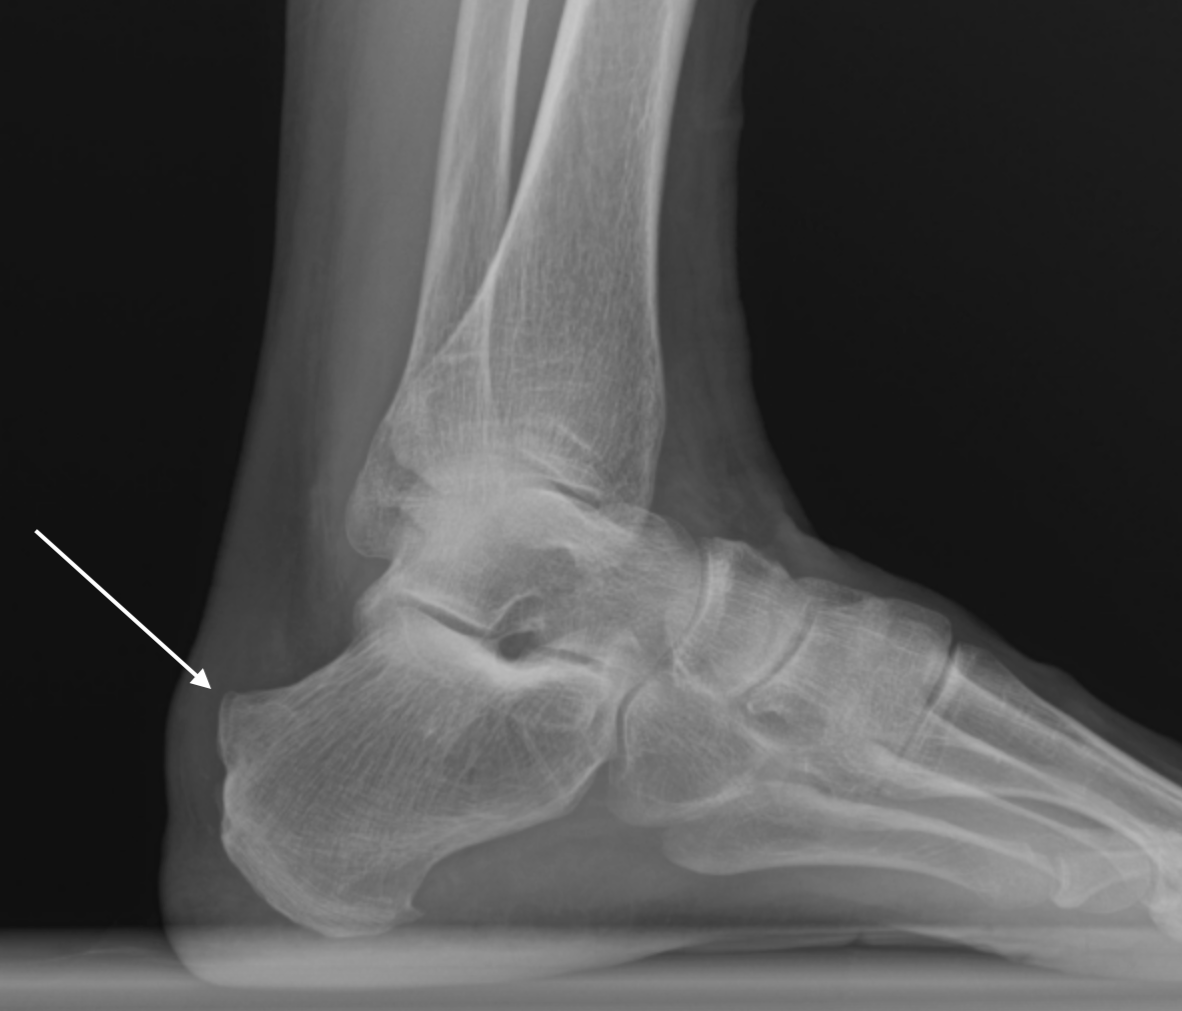

Image Interpretation: Chronic insertional and pre-insertional Achilles tendinosis associated with a Haglund's deformity. There is subcortical cystic change at the level of the Haglund deformity, consistent with chronic Achilles tendon pathology. Partial tearing of the deep fibers of the Achilles tendon is noted adjacent to the bony prominence. A mild retrocalcaneal bursal effusion is also present.